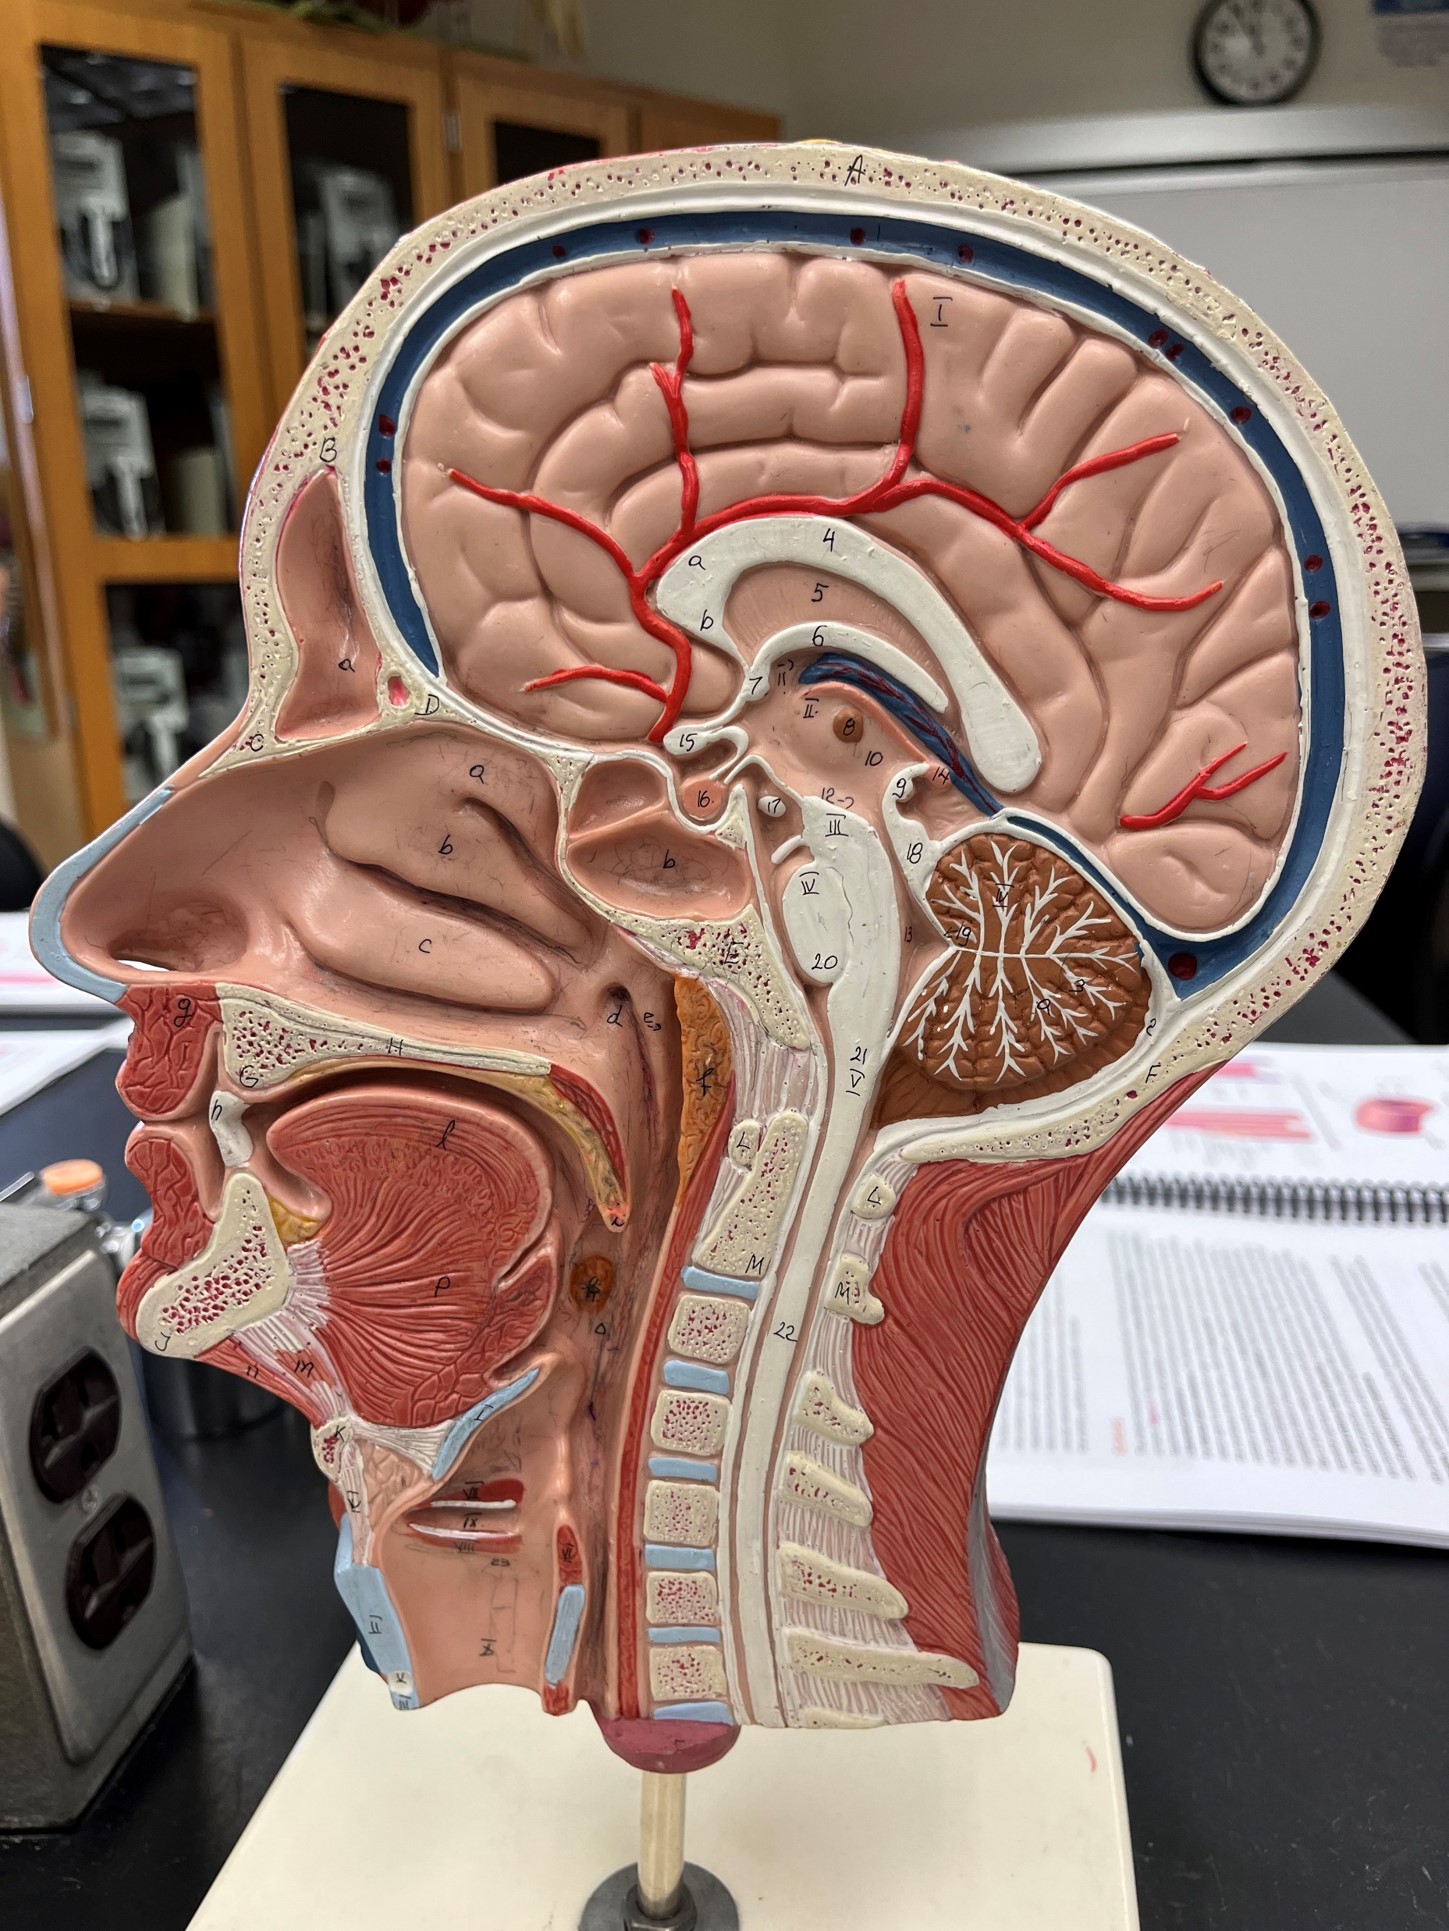

common carotid artery

• An artery of the head and neck.

• Originates from the brachiocephalic trunk (R.) or the aortic arch (L.).

• Supplies the head and neck through its branches.

• Originates from the brachiocephalic trunk (R.) or the aortic arch (L.).

• Supplies the head and neck through its branches.

external carotid artery

• An artery of the head and neck.

• Originates from the common carotid artery.

• Supplies the extracranial structures through its branches.

• Laterally, the anteriormost artery of the neck.

• Originates from the common carotid artery.

• Supplies the extracranial structures through its branches.

• Laterally, the anteriormost artery of the neck.

internal carotid artery

• An artery of the head and neck.

• Originates from the common carotid artery.

• Supplies the cerebrum through its branches.

• Laterally, the middle artery of the neck.

• Originates from the common carotid artery.

• Supplies the cerebrum through its branches.

• Laterally, the middle artery of the neck.

vertebral artery

• An artery of the head and neck.

• Originates from the subclavian artery.

• Supplies the spinal cord, meninges, and neck muscles.

• Laterally, the posteriormost artery of the neck.

• Originates from the subclavian artery.

• Supplies the spinal cord, meninges, and neck muscles.

• Laterally, the posteriormost artery of the neck.

internal jugular vein

• A vein of the head and neck.

• Drains the brain, face, and neck.

• Empties into the subclavian vein.

• Laterally, the anteriormost vein of the neck.

• Drains the brain, face, and neck.

• Empties into the subclavian vein.

• Laterally, the anteriormost vein of the neck.